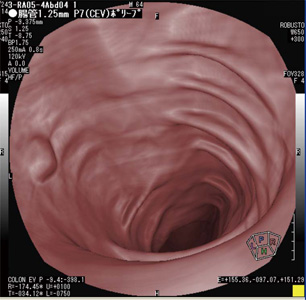

大腸内部の壁面を観察する表示モードは3種類から選択できる。図2 aに示す仮想内視鏡表示モードは,大腸内部の形状を観察する場合に有効である。壁面の凹凸を観察することで大腸ポリープなどの存在確認が行え,さらに,ポリープなどの突起物の距離計測も行える。図2 bでは,ポリープの縦・横方向の距離を計測したものである。計測した結果は,画像上の左側に数値で表示され,突起物の大きさの推測が可能となっている。

図2 仮想内視鏡画像  a:仮想内視鏡表示モード

b:距離計測機能